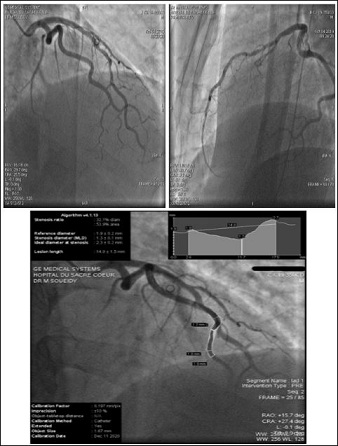

ECG was immediately obtained, it consistently showed (LBBB) during chest pain episode (Figure 2). Patient was started on aspirin 325 mg, loading dose of Ticagrelor 180 mg, heparin drip, and was subsequently taken for emergent coronary angiogram. The coronary angiogram showed a 50% non obstructive atherosclerotic plaque of the mid-LAD (Figure 3), calculated using Quantitative Coronary Angiography (QCA). A trial of intracoronary nitroglycerin fails to relieve the stenosis as well as the chest pain, which may argues against vasospastic mechanism of his pain .The lack of availability of IVUS or FFR in the catheterization laboratory is a limitation step. A high sensitivity cardiac troponin value turned negative for 2 sets. Echocardiogram showed normal left ventricular ejection fraction without any regional wall motion abnormalities.

Figure 3: Coronarography showed the non obstructive coronary plaque of the mid LAD. (4a-RAO CRA viex/4b-LAO CAU view) using the QCA showed a 53% stenosis ratio.